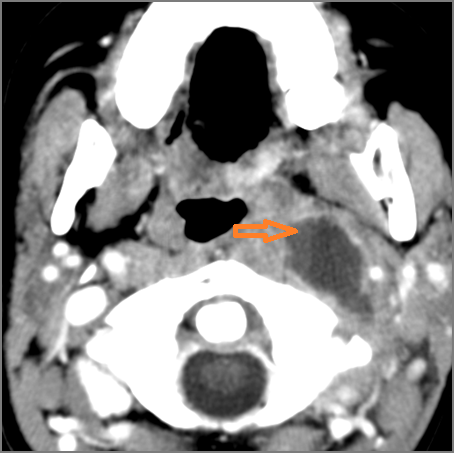

Retropharyngeal Lymph Nodes

If there is suppurative retropharyngeal adenopathy what is the maximum short axis dimension of the largest suppurative node. MEASUREMENT

Hypopharynx, Larynx, Deep Neck and Entire Retropharyngeal Space

There is edema within the adjacent deep neck, retropharyngeal and/or prevertebral spaces.

There is abscess within the adjacent deep neck, retropharyngeal and/or prevertebral spaces.